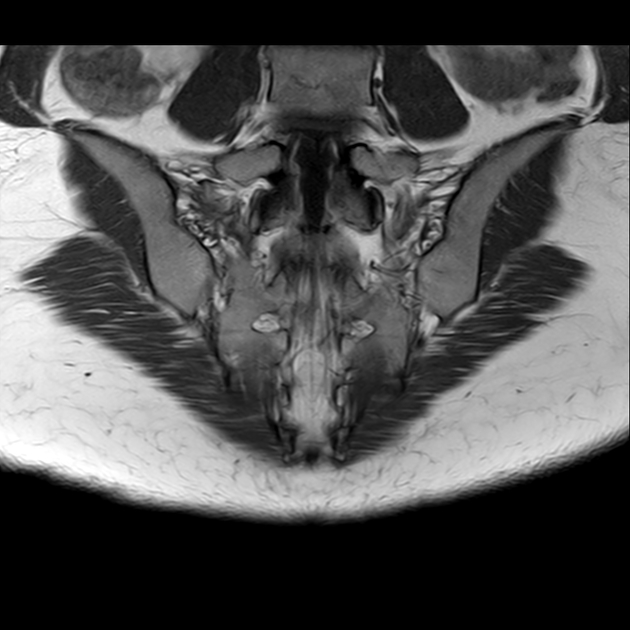

磁共振检查:

磁共振影像表现

2、单侧或双侧骶骨翼骨皮质断裂,见迂曲纵行骨折线,大致与骶髂关节平行(双侧多见);

3、骶骨体部看见骨折线

4、冠状位上述骨折形成 “H”型 ,故有人称东风本田征(为了方便记忆)

6、磁共振上可以发现骨折线周边明显的骨髓水肿,增强扫描明显强化